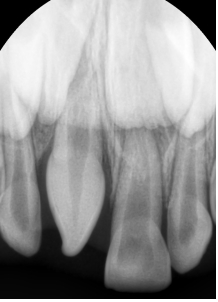

¾Õ´Ï°¡ ¹ú¾îÁö°í »ß¶Ô¾îÁ® Àִ ȯÀÚ¿¡¼ X-ray¸¦ ÃÔ¿µÇÏ¿´´õ´Ï °úÀ×Ä¡°¡ ¸Åº¹µÇ¾î ÀÖ´Â °ÍÀÌ º¸ÀÔ´Ï´Ù.

Ä¡¾Æ »Ñ¸® ¾ÕÂÊ¿¡ ¸Åº¹µÇ¾î ÀÖ´Â °úÀ×Ä¡·Î ÀÎÇØ ¾Õ´Ï »çÀ̰¡ ¹ú¾îÁö°í, ¿À¸¥ÂÊ ¾Õ´Ï°¡ »ß¶Ô¾îÁø ä·Î

¸ÍÃâÇÏ¿´½À´Ï´Ù.

Á¤Áß°úÀ×Ä¡ÀÇ 75%´Â ¸Åº¹µÈ »óÅÂÀ̱⠶§¹®¿¡ ¸ð¸£°í Áö³»´Ù°¡,

X-ray ÃÔ¿µ¿¡¼ ¿ì¿¬È÷ ¹ß°ßµÇ´Â °æ¿ì°¡ ¸¹½À´Ï´Ù.